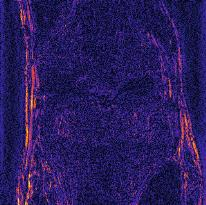

Recently, deep neural networks have greatly advanced undersampled Magnetic Resonance Image (MRI) reconstruction, wherein most studies follow the one-anatomy-one-network fashion, i.e., each expert network is trained and evaluated for a specific anatomy. Apart from inefficiency in training multiple independent models, such convention ignores the shared de-aliasing knowledge across various anatomies which can benefit each other. To explore the shared knowledge, one naive way is to combine all the data from various anatomies to train an all-round network. Unfortunately, despite the existence of the shared de-aliasing knowledge, we reveal that the exclusive knowledge across different anatomies can deteriorate specific reconstruction targets, yielding overall performance degradation. Observing this, in this study, we present a novel deep MRI reconstruction framework with both anatomy-shared and anatomy-specific parameterized learners, aiming to "seek common ground while reserving differences" across different anatomies.Particularly, the primary anatomy-shared learners are exposed to different anatomies to model flourishing shared knowledge, while the efficient anatomy-specific learners are trained with their target anatomy for exclusive knowledge. Four different implementations of anatomy-specific learners are presented and explored on the top of our framework in two MRI reconstruction networks. Comprehensive experiments on brain, knee and cardiac MRI datasets demonstrate that three of these learners are able to enhance reconstruction performance via multiple anatomy collaborative learning.